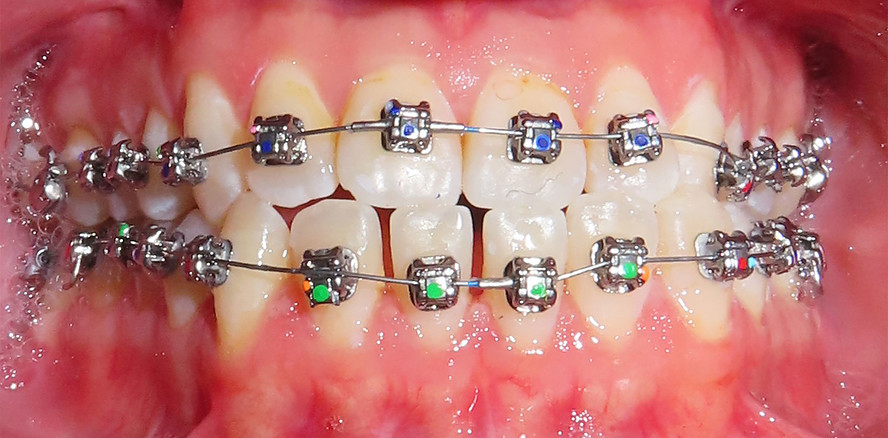

Apparative Versorgung

Die Behandlung erfolgte mittels einer festsitzenden Multibracketapparatur unter Verwendung passiver selbstligierender Brackets (Damon Ultima System) im Ober- und Unterkiefer.

Zur sagittalen Korrektur wurden intermaxilläre Klasse III-Gummizüge eingesetzt.

Bracketpositionierung und Torque-Strategie

Oberkiefer

• Zähne 12–22: Brackets mit Retroklinations-­Torque

• Zähne 13 und 23: Brackets mit proklinationsförderndem (Brocline-)Torque

Ziel war die kontrollierte Retrusion der oberen Front bei gleichzeitiger Sicherung der Eckzahnbreite.

Unterkiefer

• Zähne 33–43: Brackets mit proklinationsförderndem Torque

Hierdurch sollte eine gezielte Proklination der unteren Front zur Verbesserung des Overjets und der sagittalen Verzahnung erreicht werden.

Zu Beginn der Nivellierungsphase wurden in beiden Kiefern 0.013" CuNiTi-Bögen eingesetzt (Abb. 4a–e).